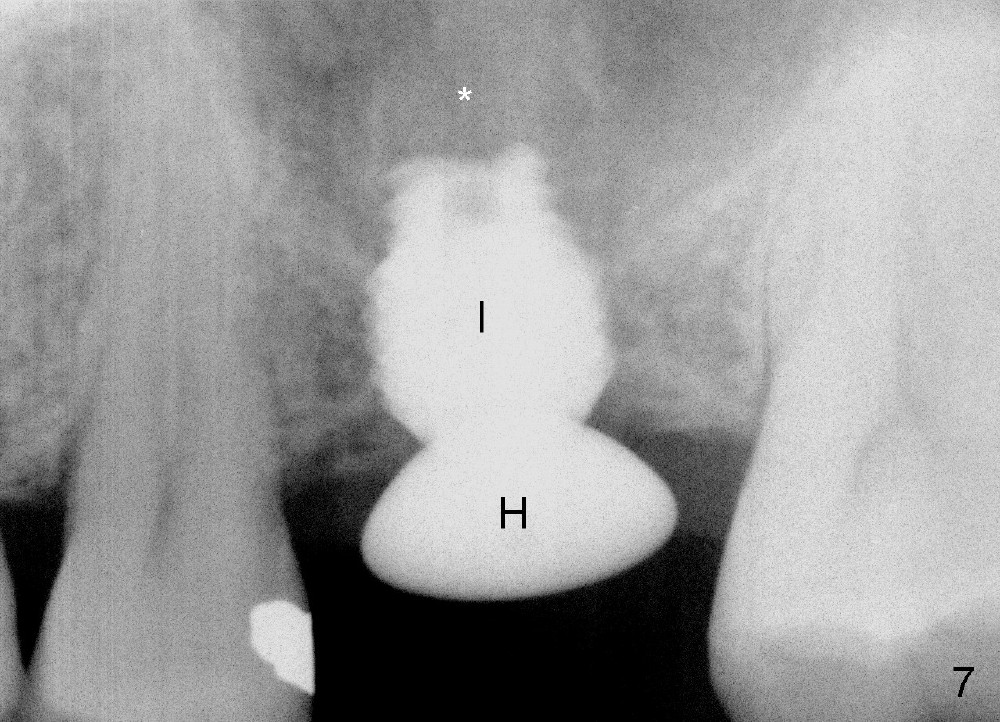

A 45-year-old man has lost the tooth #14 for a while (Fig.1); bone height is 5.4 mm. An extra wide and short implant is planned. Torus palatinus is large, suggesting that bone density should be high. A 6 mm tissue punch is chosen, but it is placed more palatal. If it were placed in the middle of the ridge, there would be no buccal keratinized gingiva (incision may avoid this issue). Additionally, the buccal portion of punch is made incomplete so that there is pedicle on the buccal side when the flap is raised (Fig.4,8: F). It is expected that the excess portion of keratinized tissue will form thick gingiva buccally. Osteotomy proves that bone is dense (Fig.2 (4.5x11 mm tap). Typical sinus lift is finished with placement of 6.4x6 mm (extra wide) bone-level implant (Fig.3, >55 Ncm). Following further torque, Fig.4 shows that the implant (I) is sub-gingival (<). Bitewings are taken to confirm that the implant plateau is at the crestal level (Fig.5,6 ^). PA shows sinus lift (Fig.7 *). The lingual aspect of the implant and healing abutment (H) is further bone grafted and covered by collagen dressing (Fig.8 *). The wound is protected with perio dressing. When the latter dislodges 7 days postop, the collagen dressing and bone graft are lost as well (Fig.10), while the buccal flap remains vital (Fig.9). The lingual exposed plateau should be able to heal normal. The collagen dressing should have been fixed in place by suture or as simple as a dental floss. There is mild nasal hemorrhage 1-2 days postop, possibly related to sinus membrane perforation and inability of Collagen Dressing to cover the perforation and contain the bone graft. When the patient returns for #9 implant placement in 3 weeks postop, the buccal flap reduces in size (Fig.11 *), while the palatal wound has healed with minimal exposure of the implant (Fig.12). Sinus graft remains in place 3 months postop (Fig.13); the buccal flap appears to have incorporated into a part of the gingiva (Fig.14). The bone density of the sinus lift appears to increase 10 days later when an abutment is placed (Fig.15 *). Although oral hygiene is pristine, there is apparent crestal bone resorption 12 months (Fig.16) and 20 months (Fig.17) post cementation, probably due to unfavorable crown/implant ratio and bruxism as well as pre-implantation bone loss (Fig.18,19). In contrast, an immediate implant in the same patient avoids pre- or post-implantation bone loss. In fact both the soft (Fig.20) and hard (Fig.21) tissues remain healthy 2 years 8 months post cementation. The sinus lift remains 3 years 8 months post cementation (Fig.22), while the crestal bone loss persists. The patients keeps complains of food impaction distal associated with bad smell 4 years 1 month post cementation. In fact the distal proximal contact is within normal limit. The bad smell is probably due to crestal bone loss (Fig.23 (pan), 24 (CT) *) and periimplantitis. Bone graft, PRF and Cytoplast membrane will be needed and fixed in place with long healing screw. When the patient returns for crown redo, he also reveals floss related gingival hemorrhage. There is pain associated with palatal sulcus probing with light gingiva erythema. Review of CT coronal section shows possible palatal (Fig.25 P) bone loss (*).